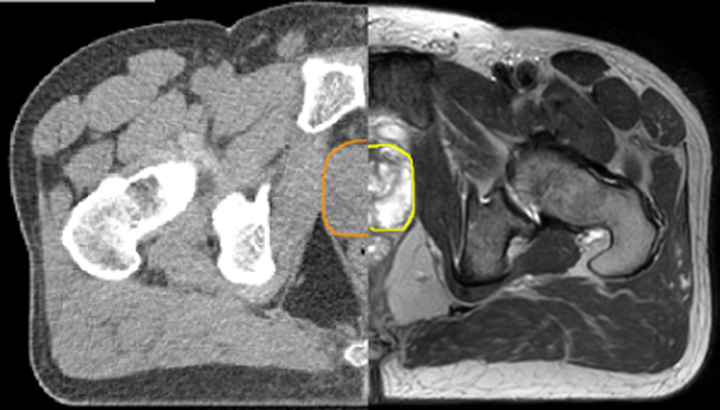

Our innovative MRCAT (MR for Calculating ATtenuation) clinical applications lets you plan radiation therapy using MRI as primary imaging modality. Within just one, fast MR exam, MRCAT provides both excellent soft-tissue contrast for target and OAR delineation and CT-like density information for dose calculations.

This not only extends the benefits of MRI’s excellent soft-tissue contrast to radiotherapy planning, but it also eliminates arduous, error-prone CT-MRI registration from the process, reducing uncertainties and complexity.

With its exceptional soft-tissue visualization capabilities and wide range of image contrasts, MRI has become a powerful tool to help more precisely define tumor boundaries. This is particularly important as it has been established that there is a high degree of uncertainty in target volume delineation, and it is even reported to represent the largest uncertainty in the entire radiotherapy process for most tumor sites**. Better visualization of the target area and nearby organs-at-risk is a key factor in enhancing target volume delineation. MRI’s expanding role also can be attributed to its functional imaging capabilities, which can inform both target characterization and treatment response.